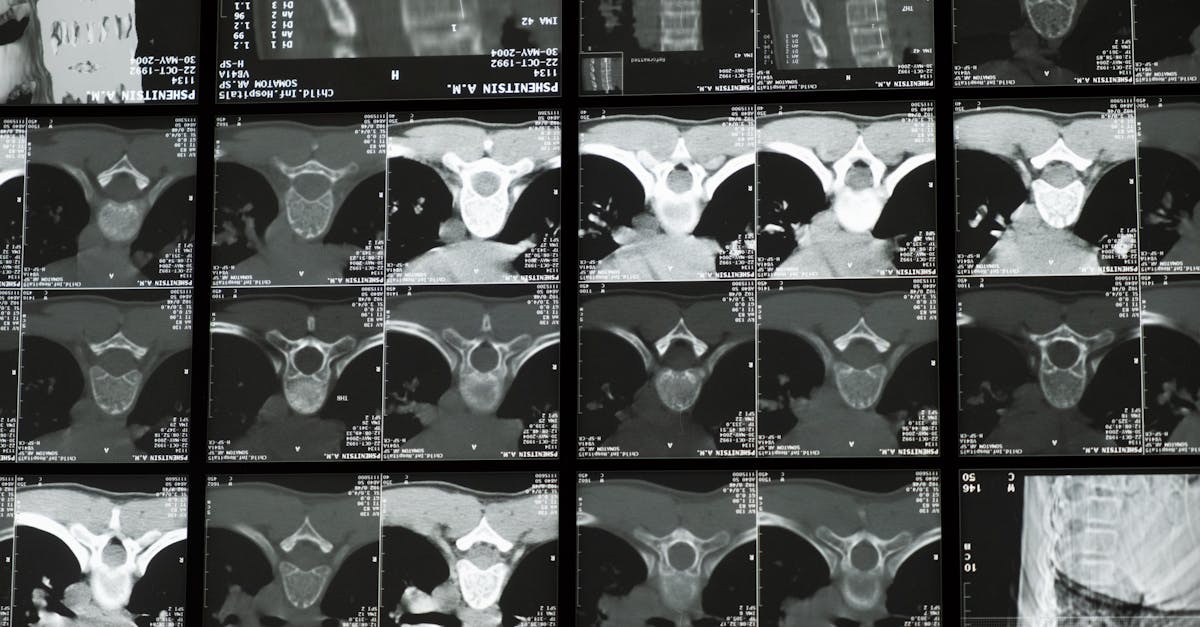

Scoliosis, characterized by an abnormal lateral curvature of the spine, can develop in children and adolescents, leading to pain and discomfort if left untreated. Although surgical options exist for severe cases, numerous non-invasive interventions have proven effective in managing and potentially preventing the progression of scoliosis. This article discusses several approaches aimed at maintaining spinal health and preventing the worsening of scoliosis.

Scoliosis, characterized by an abnormal curvature of the spine, can have profound implications on an individual’s health and well-being. While surgical options exist for more severe cases, an increasing number of families are turning to non-invasive interventions as first-line treatments. Among these approaches, the cornerstone lies in proactive strategies aimed at preventing the progression of scoliosis through appropriate management and lifestyle adaptations.